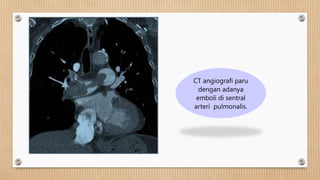

CT angiografi paru

dengan adanya

emboli di sentral

arteri pulmonalis.